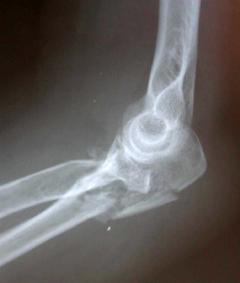

Περίπτωση 2ου ασθενούς

Προεγχειρητική